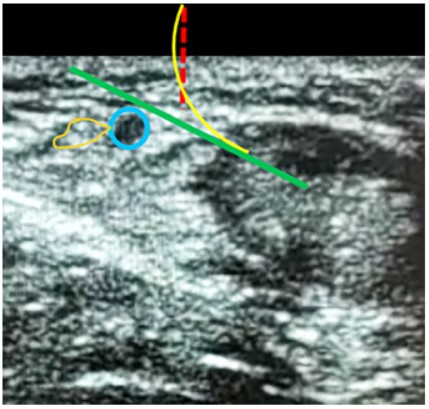

Se identifico el intervalo de la lesión en el tendón de Aquiles (Figura 2) y la trayectoria del nervio sural y su vena satélite (safena menor) mediante ecografía. Para identificar la vena fue de utilidad realizar compresión sobre los tejidos blandos y ver su colapso (Figura 3) (Figura 4).

Figura 4. Ecografía corte transversal al tendón: En azul se visualiza la vena safena menor sin compresión (izquierda) y con compresión derecha (en amarillo se identifica el nervio sural.

Figura 7. Ecografía, corte transversal al tendón: en azul se identifica la vena safena menor y en naranja el nervio sural. La línea punteada roja, representa la incisión en piel. La fecha continua verde representa el trayecto de la aguja de referencia posterior al nervio y a la vena. La línea curva amarilla indica el trayecto de la aguja de sutura, pasando por la incisión y siempre más superficial a la aguja de referencia. TA: Tendón de Aquiles.